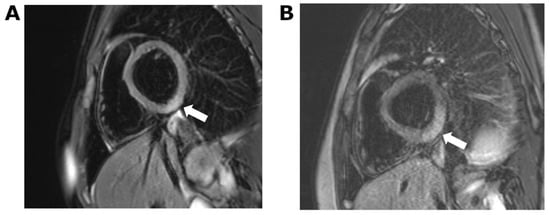

3. Case 2